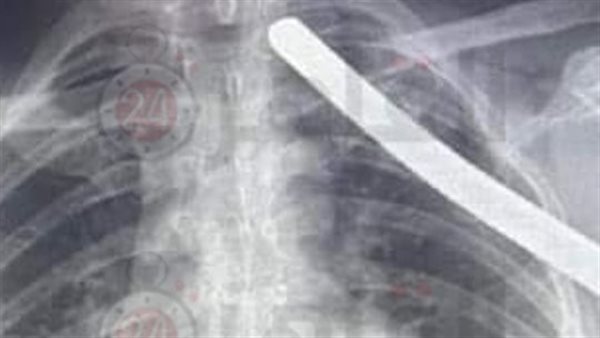

أشار رئيس قسم جراحة القلب بمستشفي قصر العيني في تصريحات خاصة لـ القاهرة 24، إلى أن عملية استخراج السيخ استمرت لمدة ساعتين، مشيرا إلى أن طول السيخ 80 سم متر، دخل في صدر العامل وخرج من الناحية الأخرى.

وأجرى أطباء قصر العيني، عملية جراحية باستخراج سيخ حديد من جسد عامل بناء، وذلك بعد مرور سيخ الحديد من صدره ما بين القلب والرئتين والشرايين الرئوية وأضخم شرايين الجسم الأورطي.